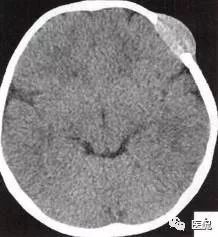

颅脑CT示:图A〜D,CT平扫示左侧额骨、蝶骨见溶骨性骨质缺损,边界清晰,周围无硬化边,伴有软组织肿块向脑外生长,边缘光滑,脑内无明显侵犯;

2.定位诊断:额骨、蝶骨均可见局限性骨质破坏,穿破颅骨内外板,见软组织肿块突向脑外;肿块与硬脑膜界限清楚,脑实质无侵犯;应考虑颅骨来源,向颅外侵犯。

②颅骨多处溶骨性破坏,穿透颅骨内外板;

③骨破坏无 硬化边,边缘光整,无膨胀;

④软组织肿块形态规则,边缘光滑;⑤脑膜及脑组织无侵犯, 表现为推压或移位。后三点均支持为良性肿块,结合年龄、实验室检查等,诊断不难。本例经病理(图I)证实为:嗜酸性肉芽肿。